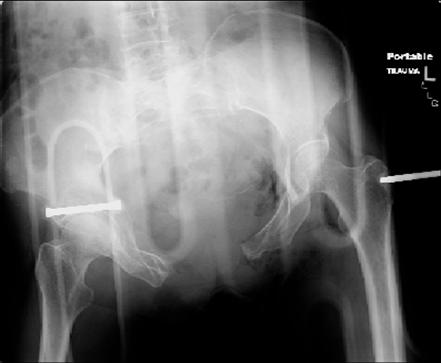

attached are images of a 70 year old female after peds versus car. her own car ran her over.

injuries are limited to the pelvis. left rami open and visible in a 10cm vertical laceration just lateral to left labia majora. wound is grossly clean. no vaginal and no urinary issues. CT scan shows widening of both SI joints anteriorly but I think this is vertically stable pattern.

pt treated that night with I/D and supra-acetabular frame to close the ring. consideration was given for SI screws bilateraly, but given time of night and other factors decision made not to proceed.

so the question is what next operatively if anything? concerns are infection, nonunion anteriorly and possible incompetence of the pelvic floor which may lead to prolapse

issues. right rami are comminuted and plating may entail ilioinguinal approach to extend plate laterally to right iliac wing. retrograde screw up right rami is an option but I am not convinced it will add much. adding SI screws very doable, but major concern is restoring anterior ring. so far wound is clean and closed over a drain, and I have no plans to open it back up and wash again.

maintaining pelvic alignment in ex-fix in 70 yo female for any length of time may be challenging.

any thoughts? would anyone plate the pubic symphysis to close the gap and leave the more lateral rami fractures alone? the most recent pelvic case on this website involved pts with suprapubic catheters and antibiotic options including resorbable beads. I wonder how many people would plate and place antibiotic beads. thanks.